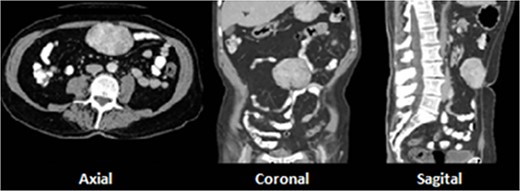

A 28-year-old male with prior history of symptomatic renal lithiasis. During clinical investigation of a persistent right lumbar pain with no other symptoms, a 54 × 43 × 37-mm non-functional adrenal incidentaloma was detected, with an absolute washout of 64% and relative washout of 56%, suggestive of adrenal adenoma (Fig. 2).